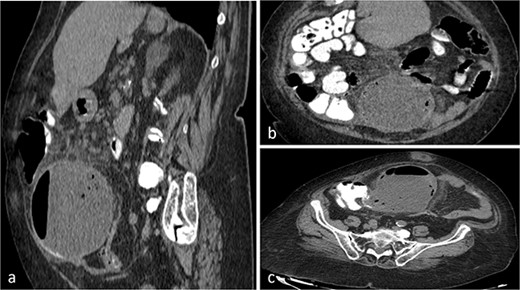

Abdominal ultrasound revealed a dense, fluid-filled mass in the right iliac region, with a significant amount of free intraperitoneal fluid adjacent to the ascending colon. The CT scan demonstrated a large lesion (98.7 × 127.3 × 107.6 mm) with a fluid-gas level that appeared to be attached at the base of the cecum (Fig. 1a–c). It extended from central pelvis to the right lower quadrant of the abdomen with no anatomical attachment to the right ovary. No regional lymphadenopathy was noted (Fig. 1a–c). Tumor markers (CEA, CA19-9 and CA125) were normal. Based on these findings, the initial differential diagnosis included ileocecal intussusception.

CT scan of the abdomen and pelvis with sagittal (a), coronal (b), axial (c) and views of a well-circumscribed, low attenuation, spherical cystic mass, with internal homogeneous non-enhancing contents and hydro-aerial levels, squalidness of surrounding fat without lymphadenopathy and slightly thickened enhancing wall with mural calcification, located anterior to the right psoas muscle contiguous with the base of the cecum.